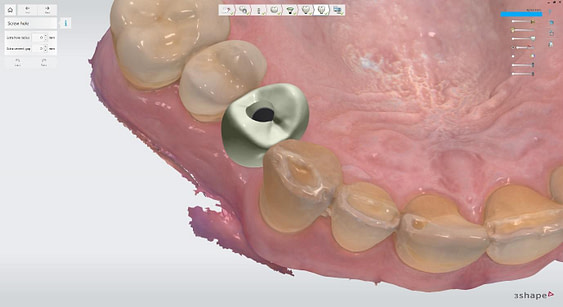

I utilized 3Shape Implant Studio, a module within the 3shape Unite Platform, to plan and execute the surgical procedure.

Pre-surgical planning began with acquiring high-quality diagnostic data, including TRIOS intraoral scans and CBCT imaging. The data was imported into 3Shape Implant Studio, where I designed a virtual crown for tooth 24 and planned the precise positioning of the implant, considering critical factors such as sinus proximity, adjacent roots, bone density, and the location of the bony defect.

Implant detection matches the scan body in the intraoral scan with the digital library. A colour scale is given to show the accuracy of the matching (Green is good).